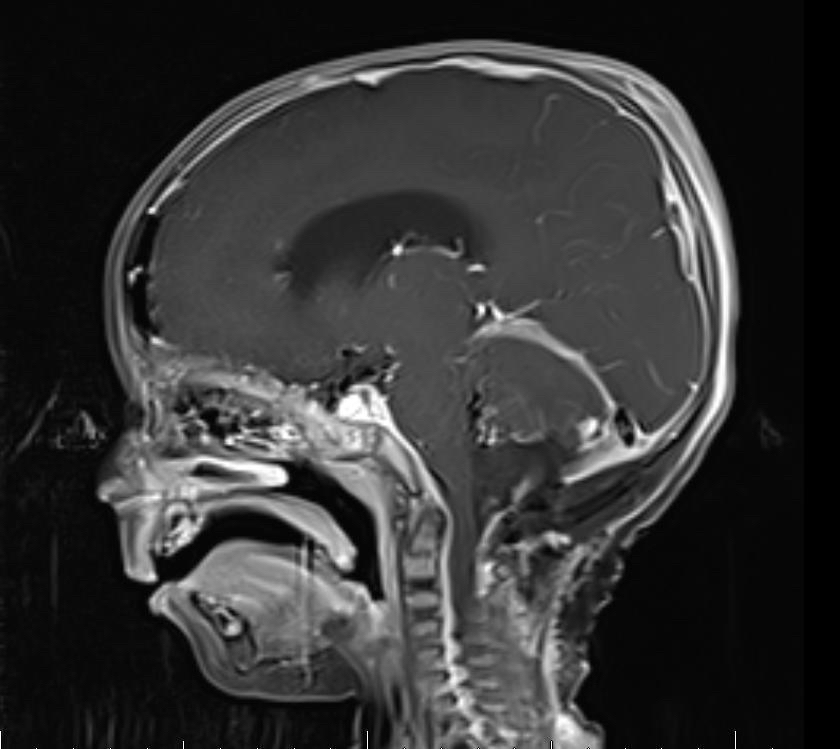

وأضافت: على الفور تم إجراء الفحص السريري والمخبري وأشعة مقطعية للرأس، والرنين المغناطيسي الذي بين وجود ورم كبير على شكل كتلة في منطقة المخيخ وتسببت له بضغط شديد على المراكز الحيوية في جذع الدماغ وأيضًا استسقاء دماغي شديد.

وأكد إجراء أشعة الرنين المغناطيسي لمنطقة الرأس مرة أخرى للتأكد من خلوه من أي بقايا لكتل ورمية، وبينت الأشعة سلامة المنطقة.